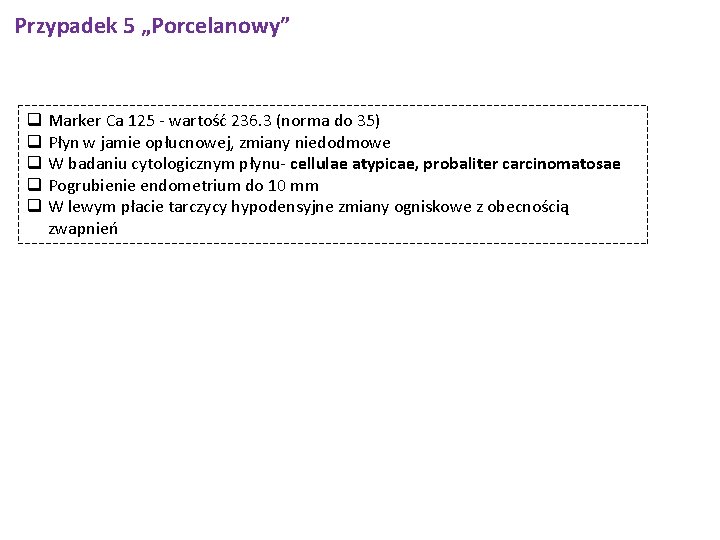

Przypadek 5 „Porcelanowy” q Marker Ca 125 - wartość 236. 3 (norma do 35) q Pęcherzyk żółciowy porcelanowy, miąższ wątroby w ok. pęcherzyka prawdopodobnie nacieczony q Płyn w jamie opłucnowej, zmiany niedodmowe q W badaniu cytologicznym płynu- cellulae atypicae, probaliter carcinomatosae q Pogrubienie endometrium do 10 mm q W lewym płacie tarczycy hypodensyjne zmiany ogniskowe z obecnością zwapnień

Przypadek 5 „Porcelanowy” q q q Marker Ca 125 - wartość 236. 3 (norma do 35) Płyn w jamie opłucnowej, zmiany niedodmowe W badaniu cytologicznym płynu- cellulae atypicae, probaliter carcinomatosae Pogrubienie endometrium do 10 mm W lewym płacie tarczycy hypodensyjne zmiany ogniskowe z obecnością zwapnień